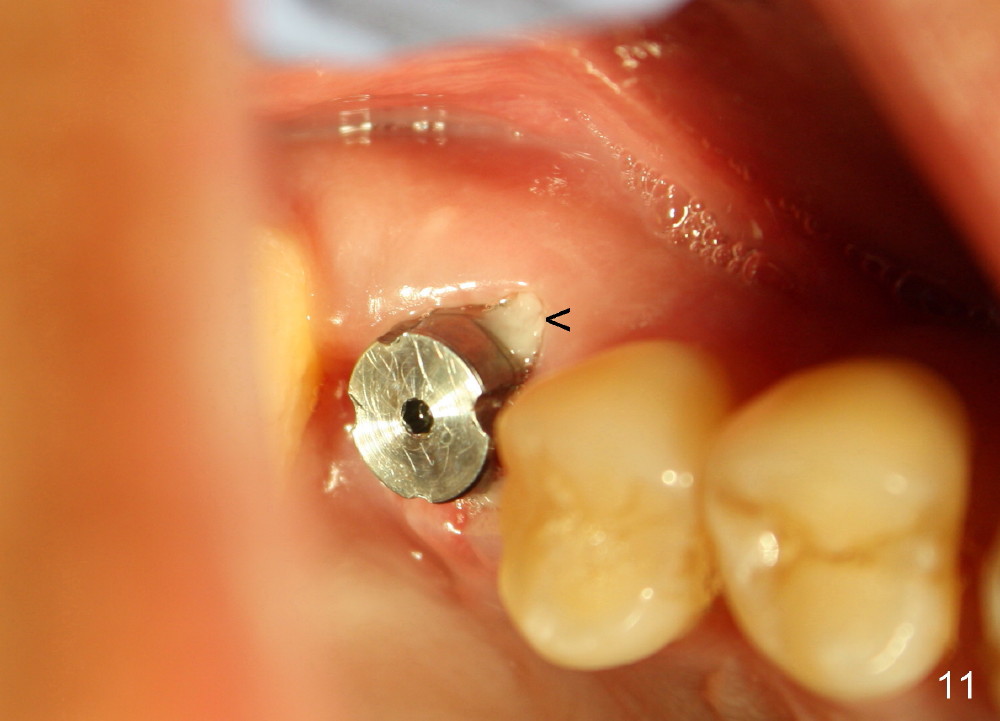

The tooth #3 has severe periodontitis with probably endodontic lesion (Fig.1,2). The patient is a 43-year-old man with apprehension of dentistry. An acute infection causes pain and tooth shift (Fig.4,5). A 7x17 mm immediate implant is planned (Fig.3). The palatal socket is shallow (Fig.6 P), corresponding to severe recessive palatal root (Fig.5 P). The osteotomy is created mainly in the buccal socket (Fig.6 B), exactly in the lingual slope of the septum. Initially osteotomes are used, followed by tap placement (Fig.7 T (4.5x20 mm at the depth of 17 mm). When the implant is placed as planned (Fig.8 I), there is more vertical contact (Fig.8 red line) than that associated with the tap (Fig.7 red line). The corresponding insertion torque is between 50 and 60 Ncm. There is only one small gap buccally, which is filled with bone graft (Fig.9 <). After the insertion of a short abutments with vertical slots (Fig.9,10 A), perio dressing is used to cover the wound. The palatal socket is expected to heal uneventfully (Fig.10 P). In fact, it does in 7 days (Fig.12 P); the bone graft in the mesiobuccal aspect is healing and stabilized (Fig.11 <). By two weeks postop, the mesiobuccal socket has healed (Fig.13 <). With removal of a diseased tooth, our body has amazing power to heal.